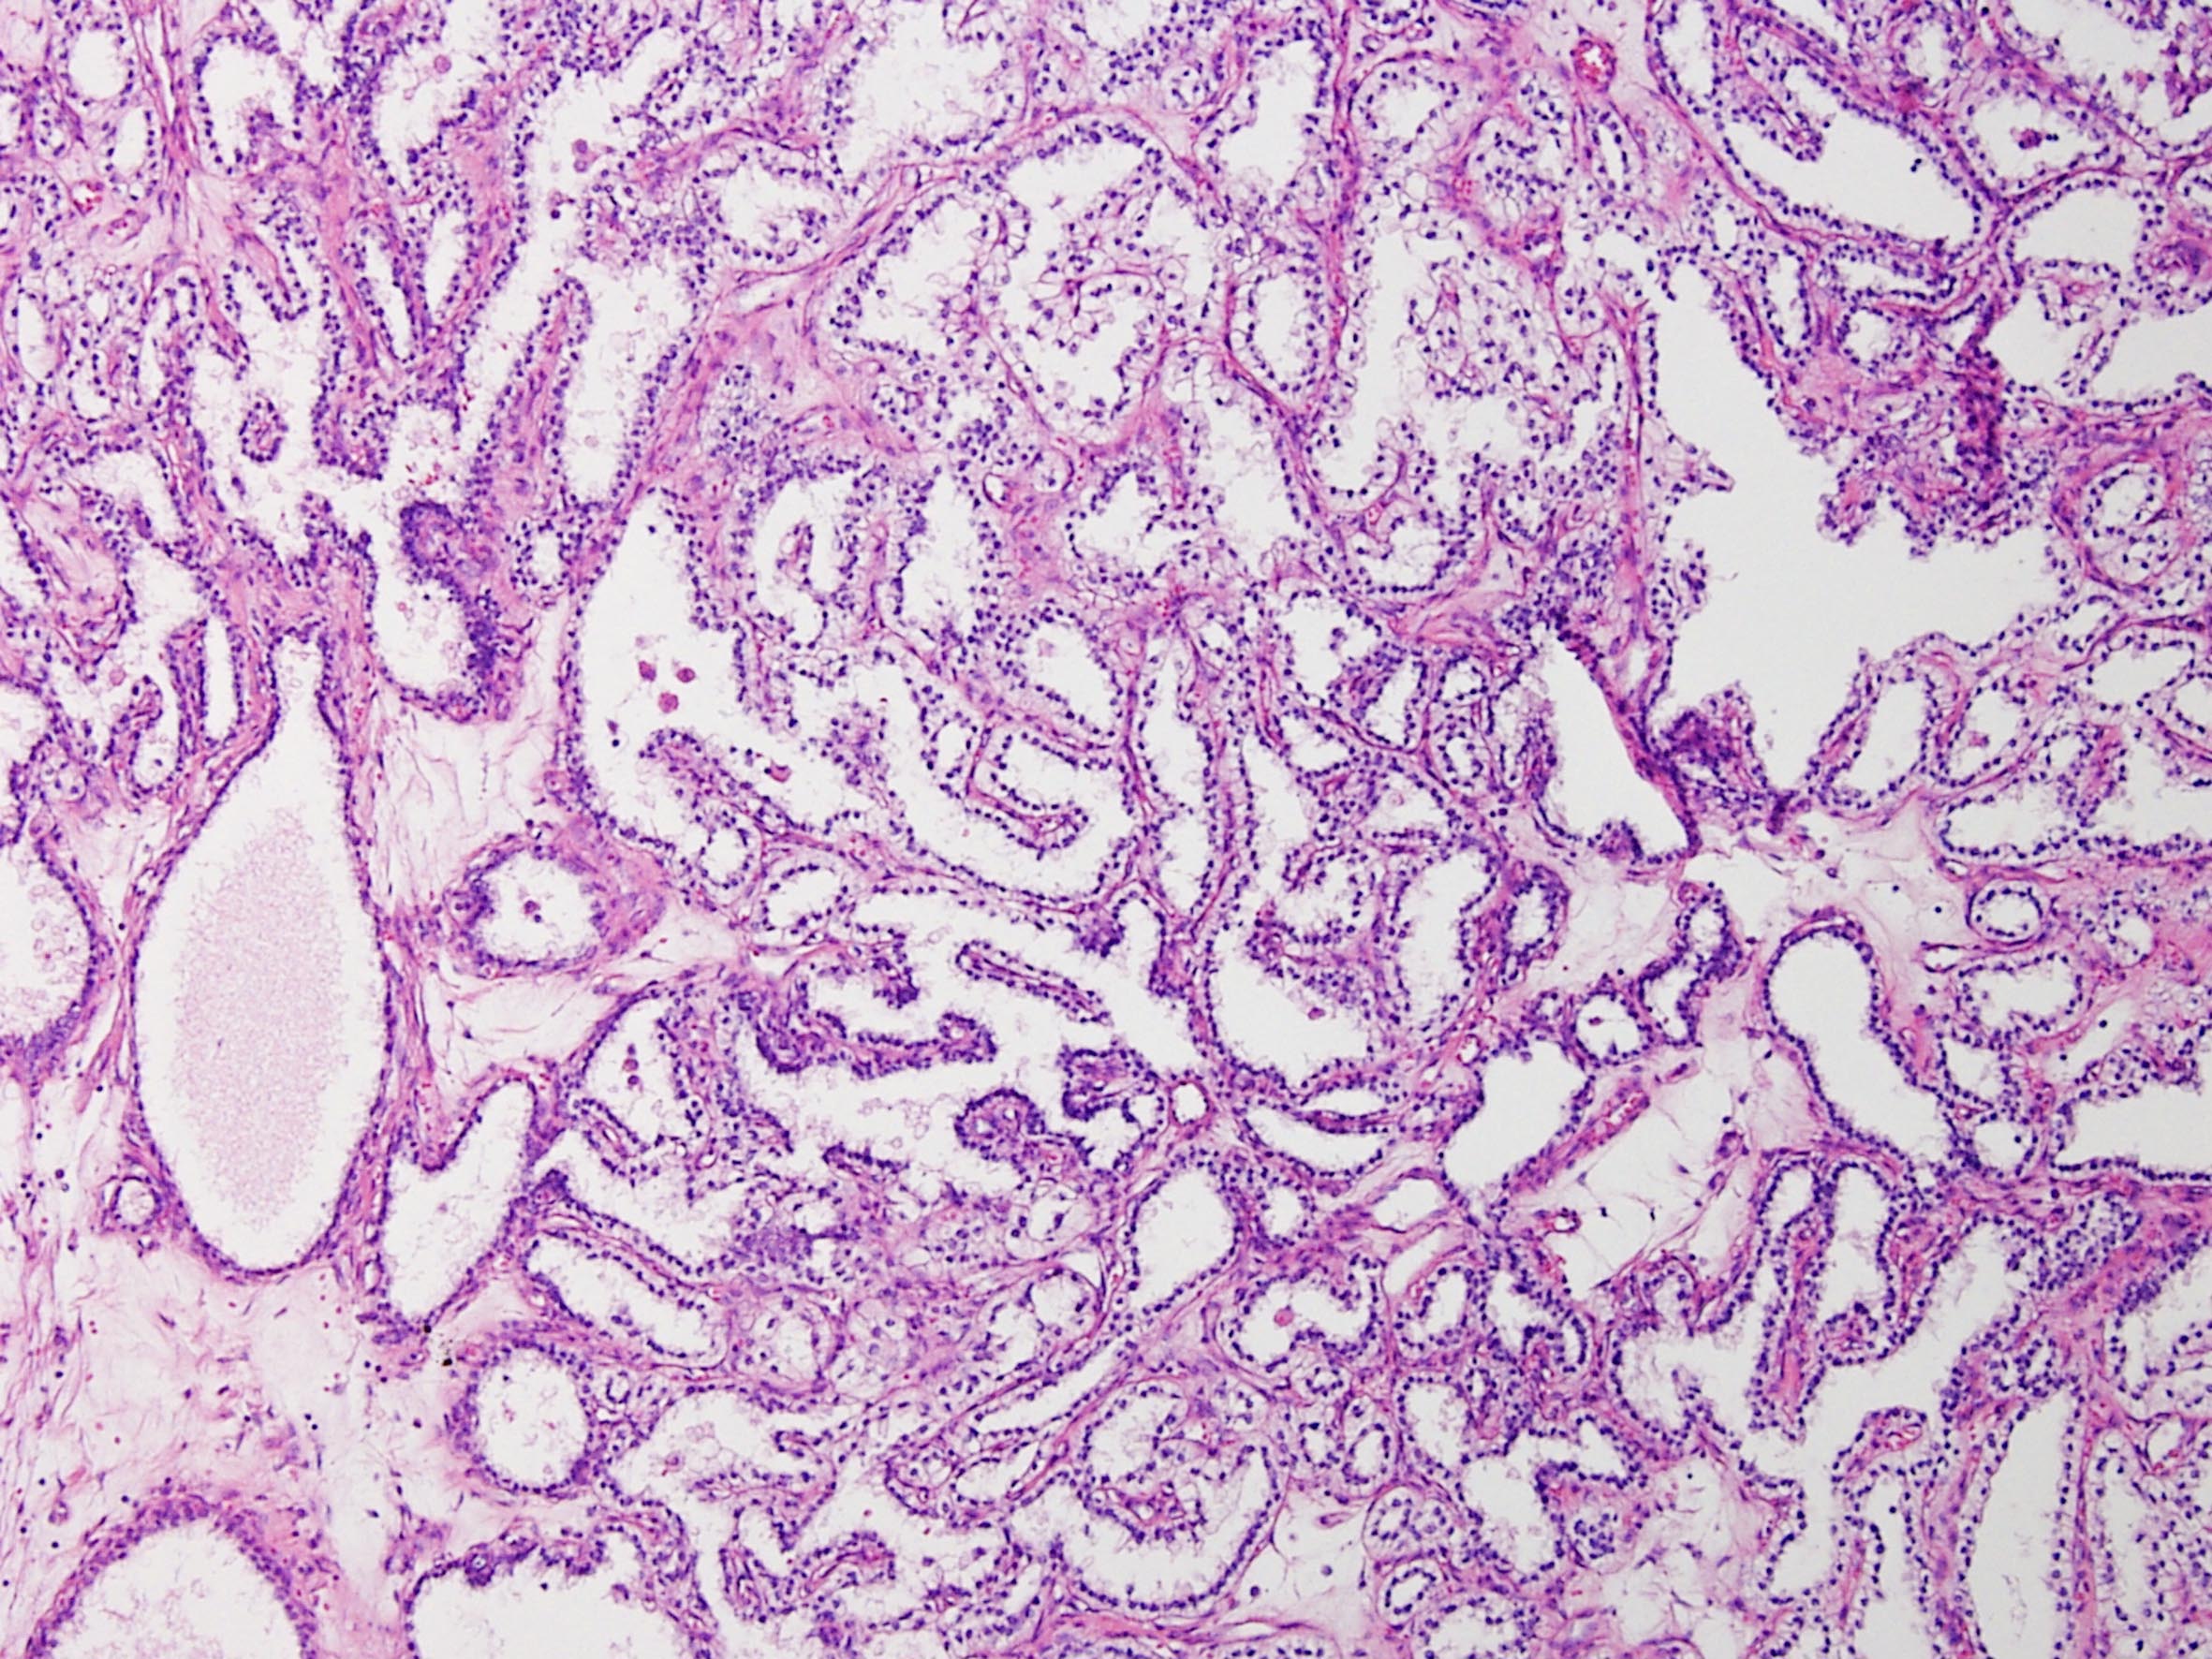

Classification of renal tumors

Case ID: 164